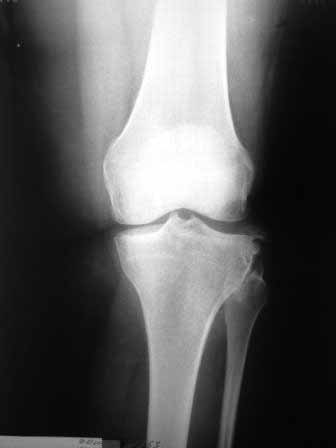

Сегодня на приеме была больная 27 лет, вес 120кг. Травма 7 лет назад - ДТП. Была ЧМТ, двухсторонний перелом пилона, обширные рваные раны бедер, голеней. Судя по нынешней картине - вывих левой голени.

Ходит практически не хромая, жалобы на неустойчивость голени при ходьбе. При стресс тестах - грубейшая несостоятельность связочного аппаратаколенного сустава. Хотелось бы услышать мнение о целесообразности пластического восстановления связок после столь длительного периоданестабильности сустава.С уважением,Leonid m

Сделайте МРТ. При таком р-гене возможен разрыв задне-латерального комплекса с выраженной нестабильностью. Тактика - пластика ЗКС, ЛКС.